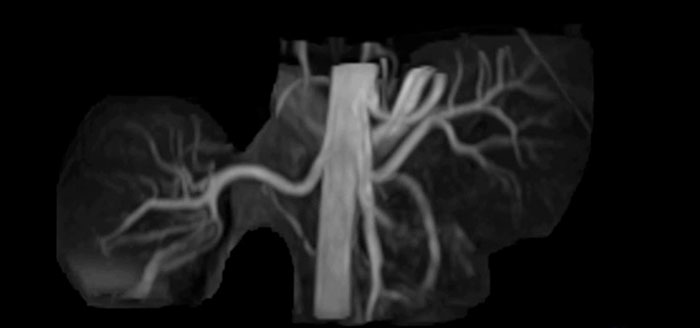

Non-contrast MRA of renal arteries

Imaging the renal arteries without contrast agent on Prodiva 1.5T.